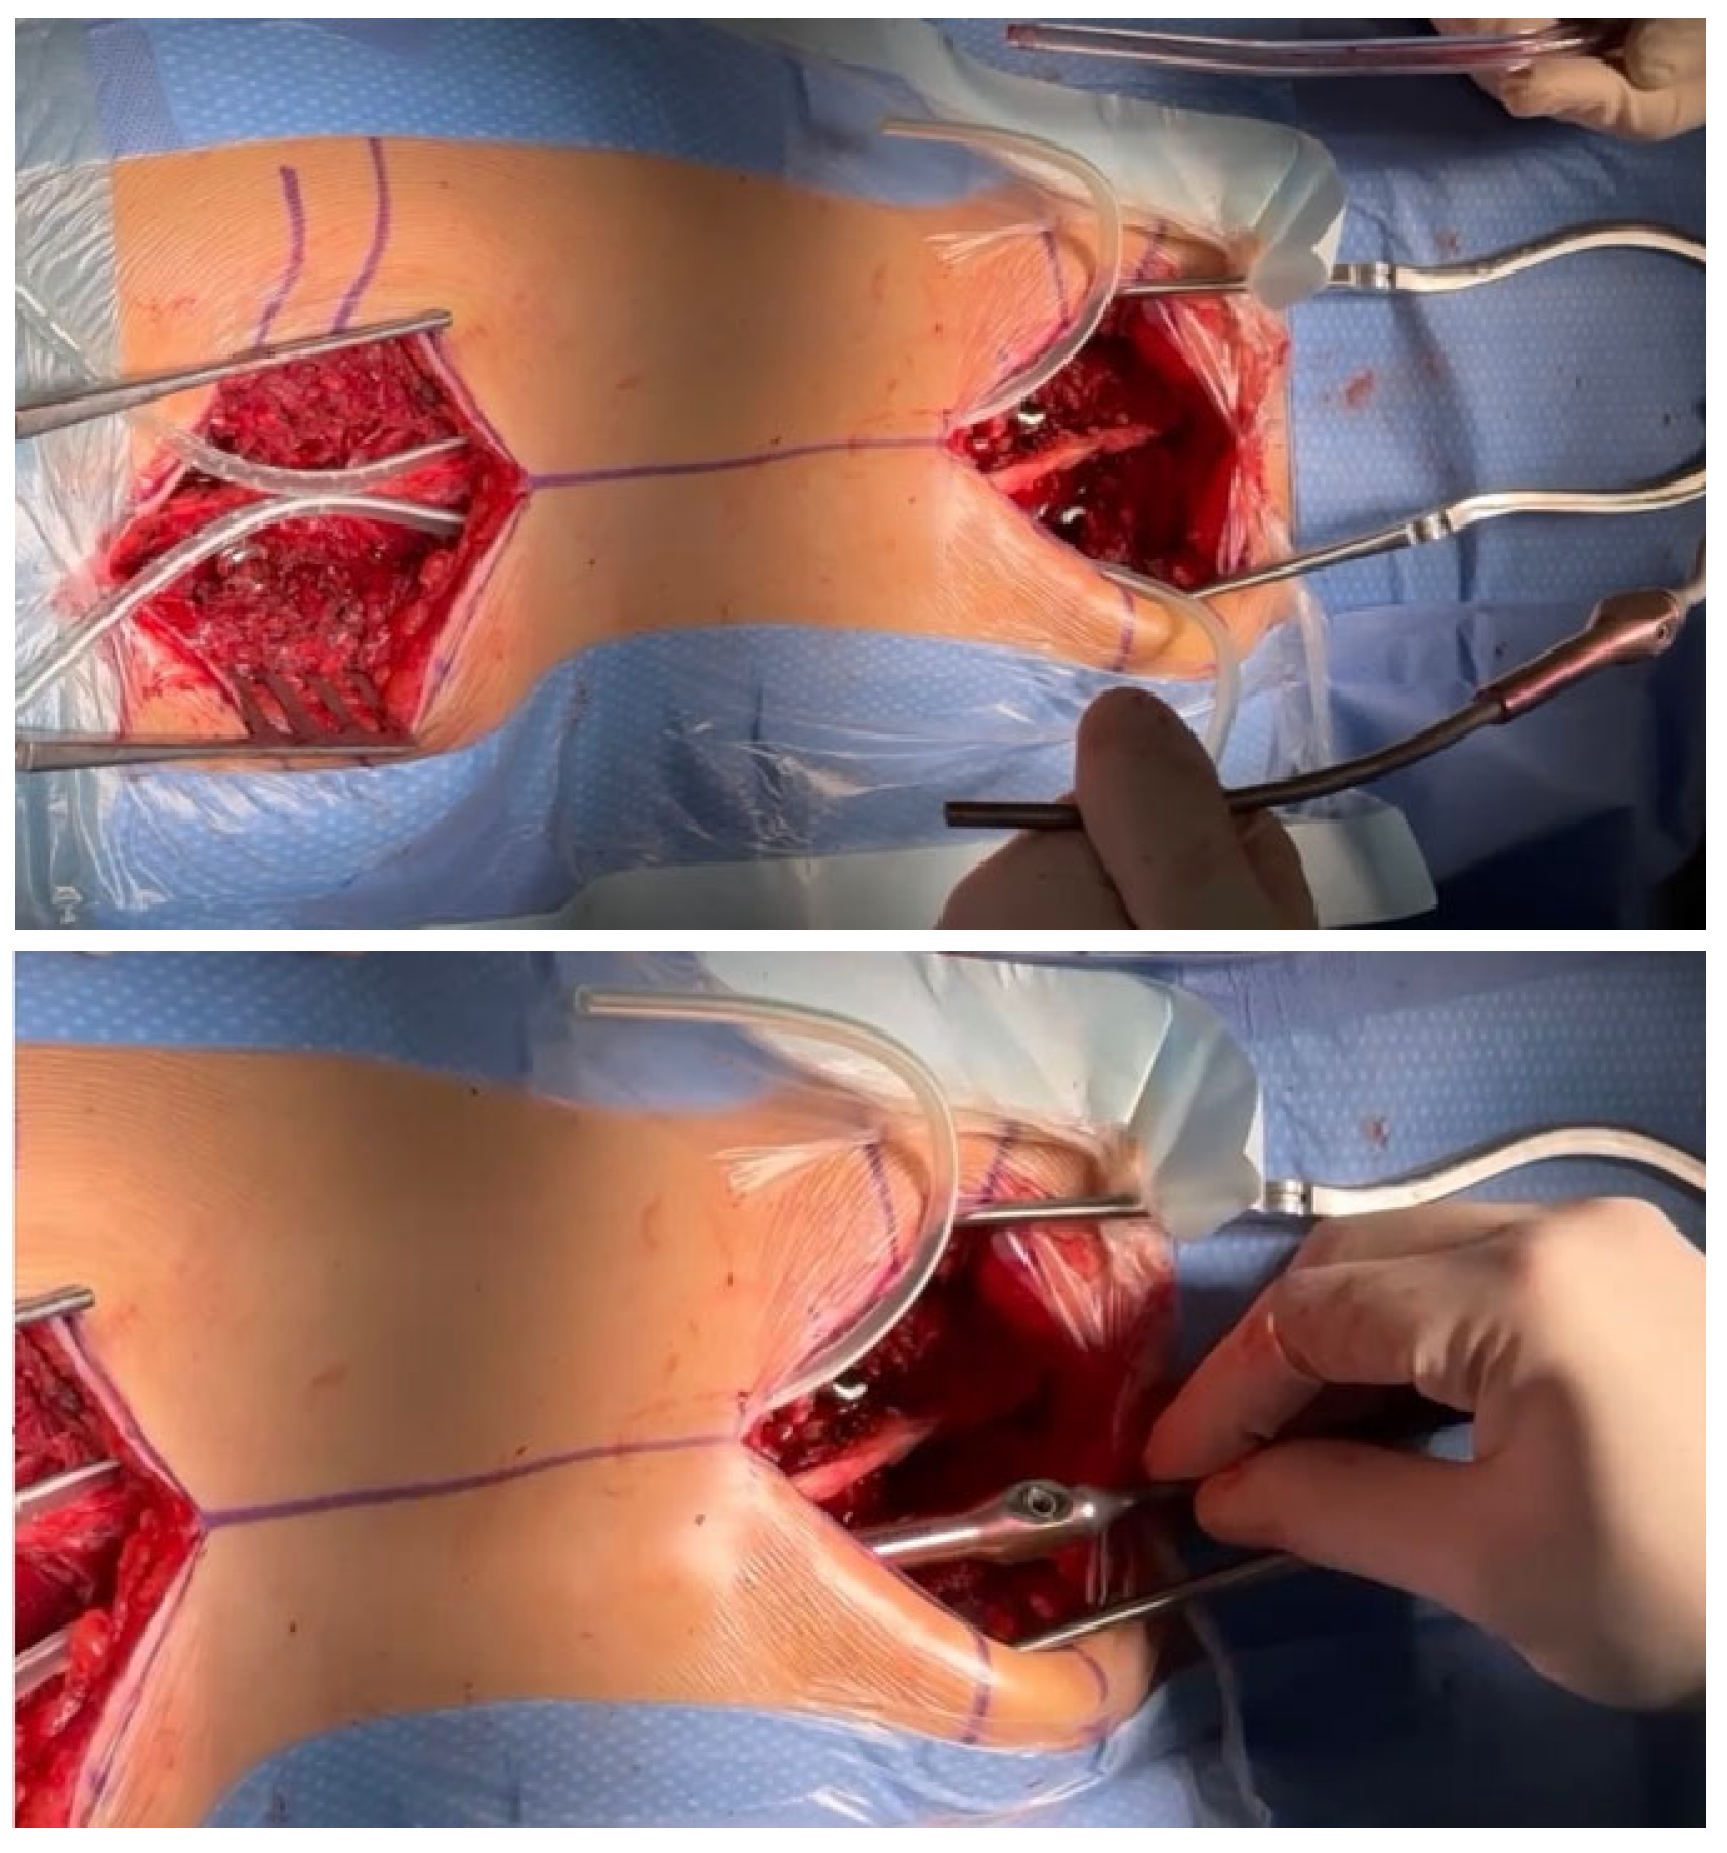

2.1. Surgical Technique